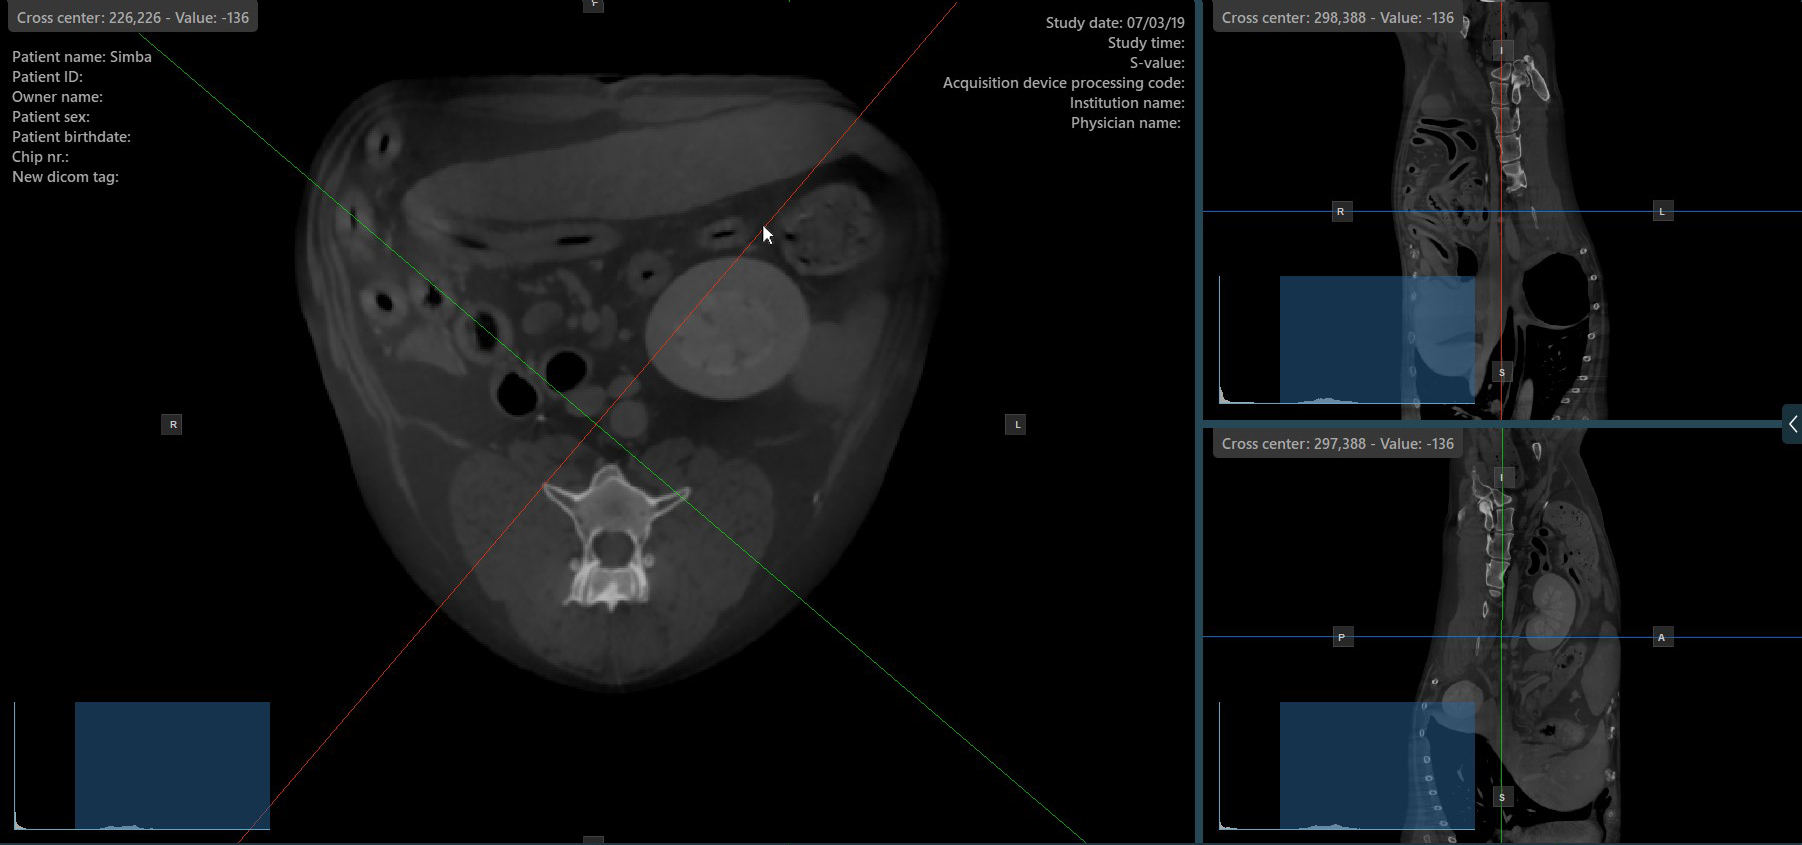

By default, each slicer can be rotated separately. The corresponding icon in the left toolbar of the CT Viewer will be deselected when the slicers are rotated individually.

Press the Perpendicular Slicers

icon in the left toolbar to activate simultaneous rotation of the slicers. Regardless of their previous orientation, the slicers are repositioned to be perpendicular to each other.

Toggle the Perpendicular Slicers

option to switch the active mode of the slicers at any time, or choose one of the Tools -> Perpendicular Slicers

or Tools -> Separate Slicers

options from the CT Viewer menu.